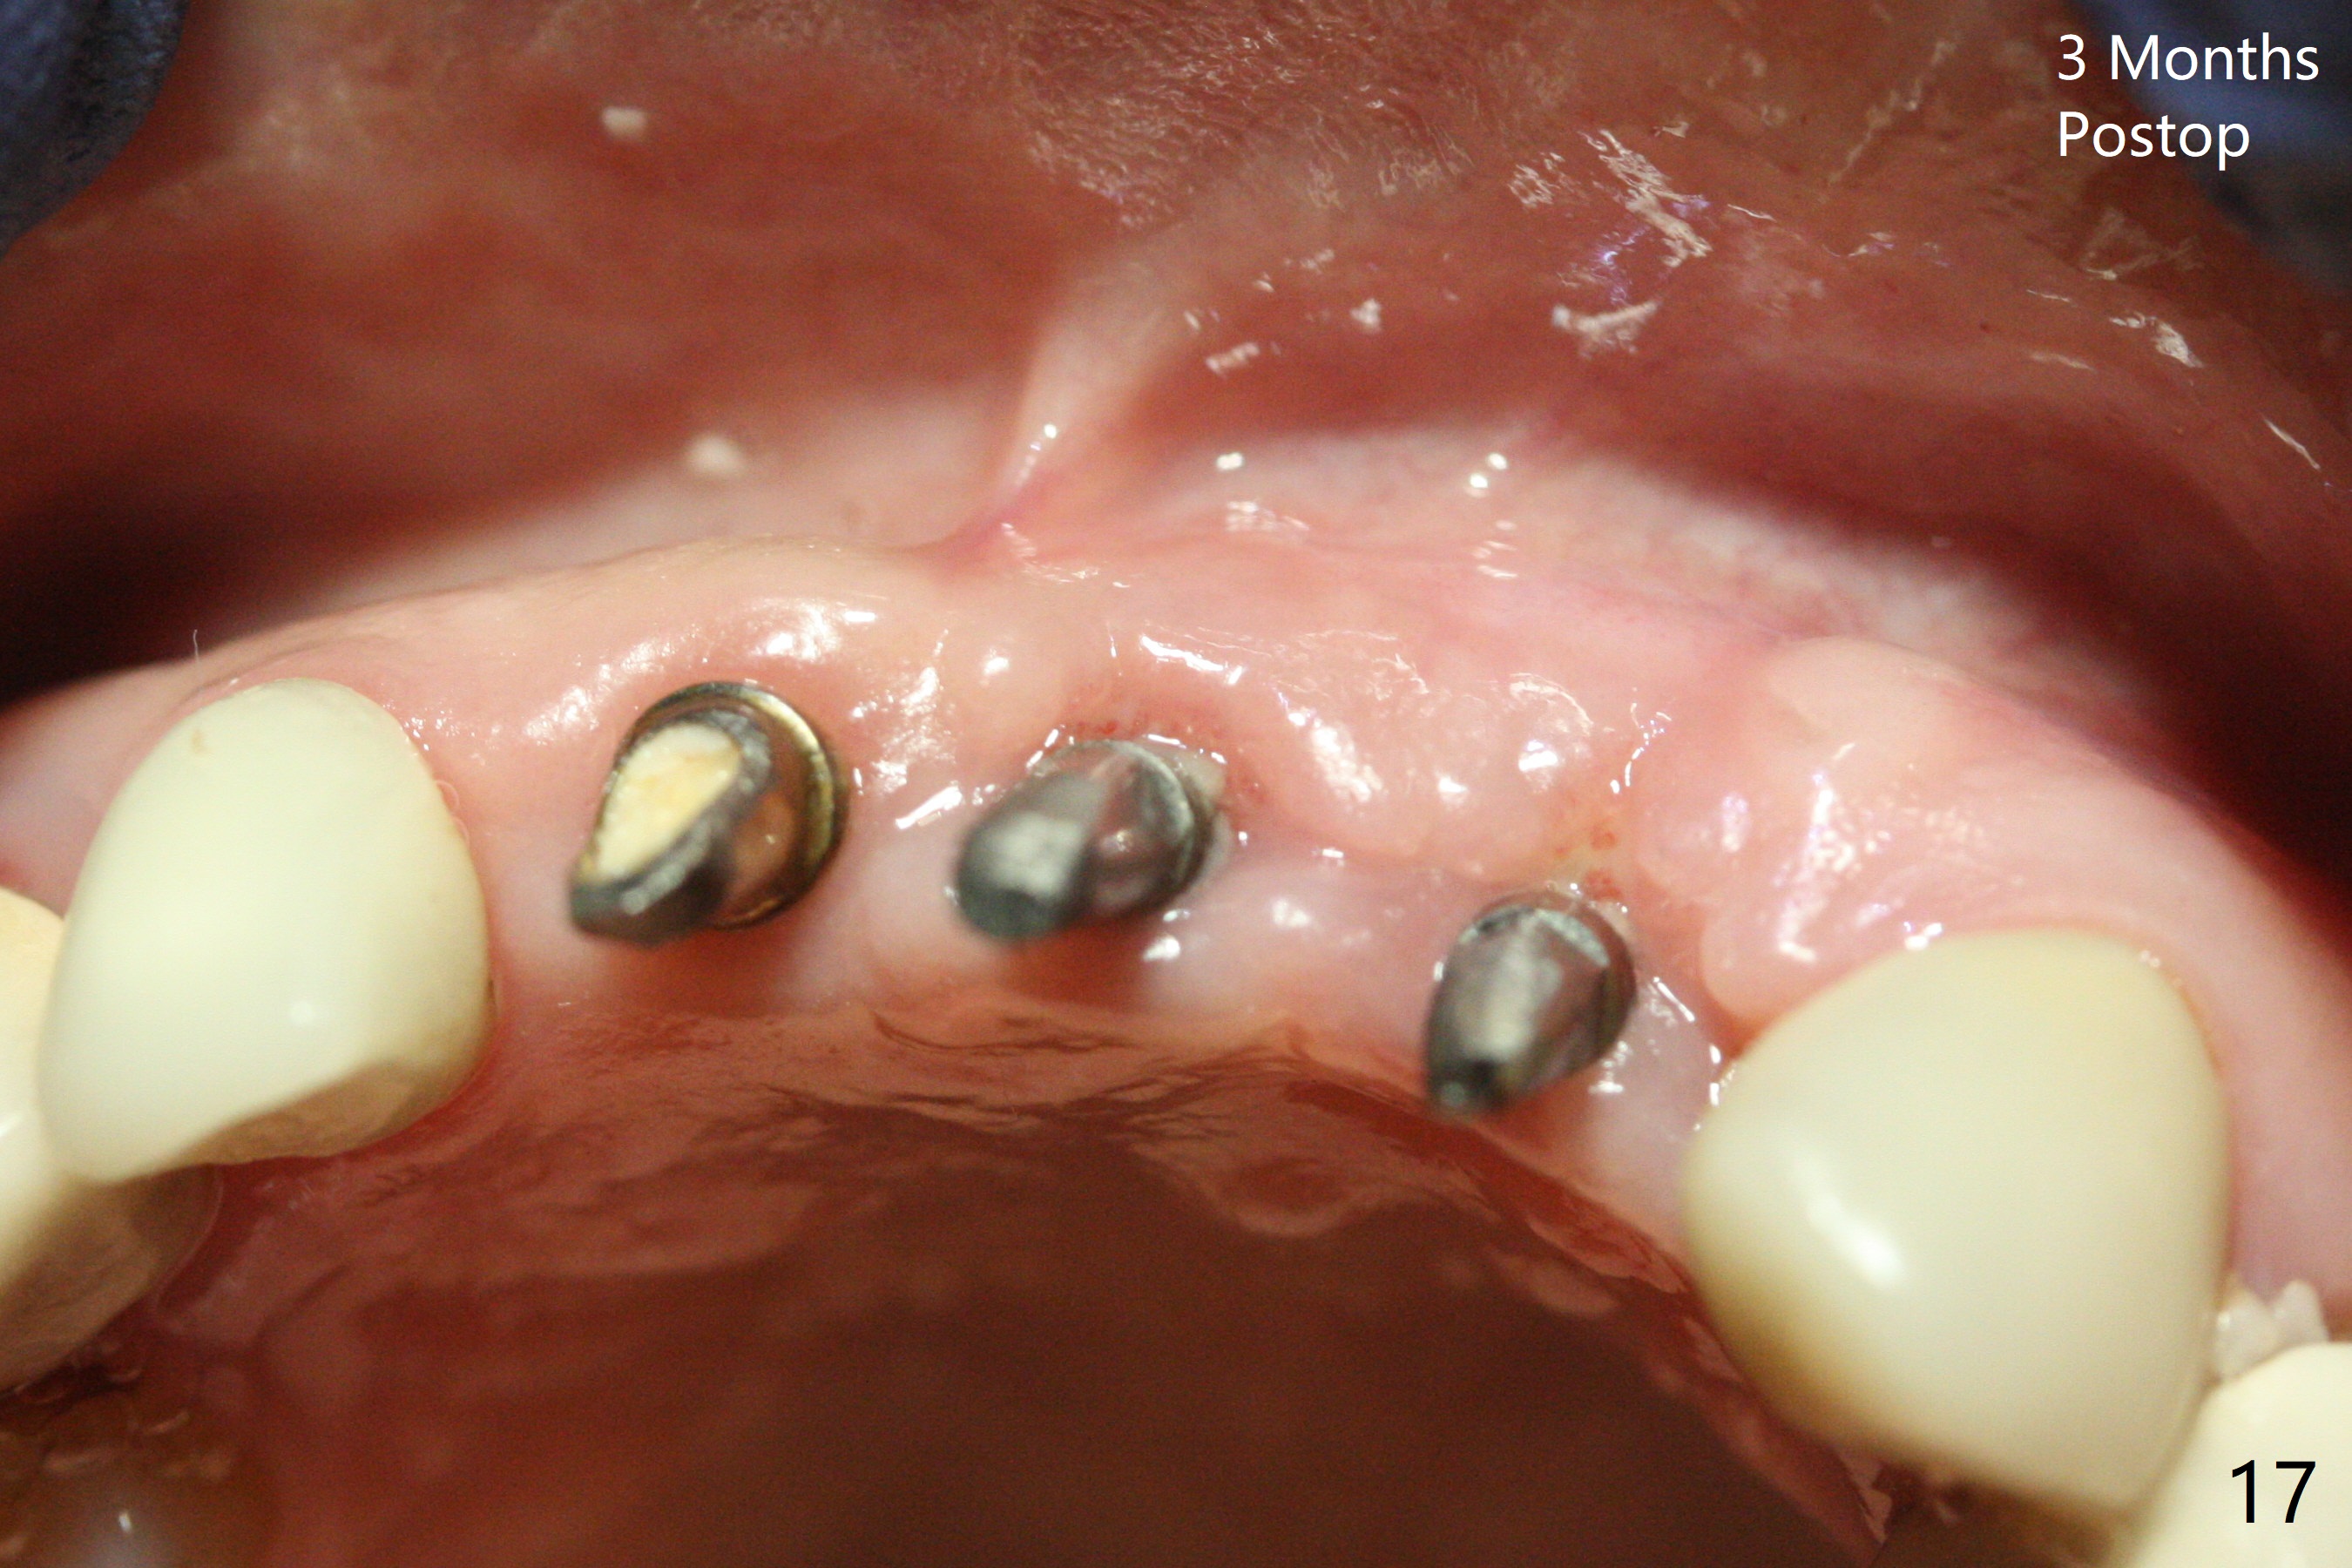

Incision shows exposure of microthreads at #9 and major threads at #10 due to buccal placement (Fig.1). There is bone palatal to the implant at #10 (Fig.2 P), to which a new implant will move. After implant removal, a narrower 1-piece implant (2.5x14(4) mm) is placed palatally at #10 (Fig.3,4) in combination of guide and free hand. At the site of #9 after implant removal, the guide is not used; a 3x17 mm angled 1-piece implant is placed with bad trajectory (Fig.5,6). After re-adjustment (Fig.7), the implant is placed at the right orientation (Fig.8). It appears that the guide is helpful. Allograft is placed mainly buccally (Fig.9,10 *), followed by a piece of collagen membrane (Fig.11). After tension release, flaps are approximated (Fig.12). The buccal gingiva at #9 and 10 recede nearly 2 months postop (Fig.13). Less recession at #9 is associated with more inflammation (Fig.14). The margin of the provisional is adjusted for gingival margin down growth and easy self cleaning with Water Pik (Fig.15). One month later, the gingival inflammation reduces, while there is no obvious buccal collapse (Fig.16,17). Impression is taken after laser gingivectomy nearly 4 months postop (Fig.18). While the gingiva around the implant at #9 is inflamed (periimplantitis?), the gingival cuff at #10 is well formed 5.5 months postop immediately before cementation (Fig.19). The buccal concavity at #10 is minimal (Fig.20). The gingival inflammation at #9 will be hopefully resolved after cementation of the final restorations (Fig.21). There appears to be new bone formation around the coronal implant threads 5.5 months postop (immediately post cementation, Fig.22). The microthreads at #9 may be not covered by the bone, the reason for the gingival erythema. The redness at #10 is asymptomatic 5.5 months post cementation (Fig.23). 粘固后两年牙槽嵴骨质并没有再生(图二十四),说明第一术中植体必须植入骨下(基台部分要长,否则难于修复),第二牙槽嵴处不应该有压力,植入2.5毫米植体,最后钻头应该是2.5毫米,骨下1-3毫米(尝试项目)。